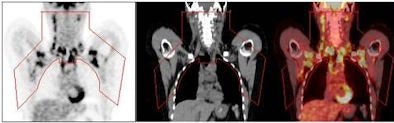

The PET/CT scans identified substantial areas of brown adipose tissue from the anterior neck to the thorax. Positive scans were seen in 76 of 1,013 women (7.5%), compared with 30 of 959 men (3.1%). Women also had a greater mass of brown adipose tissue and higher FDG uptake activity.

| Brown adipose tissue (BAT) volume and activity can be quantified in a "fat map." Regions of interest (red outline) include the principal cervical, supraclavicular, and superior mediastinal BAT depots, from left to right, in the PET, CT, and fused PET/CT images. Image courtesy of Dr. Aaron Cypess, Joslin Diabetes Center. |